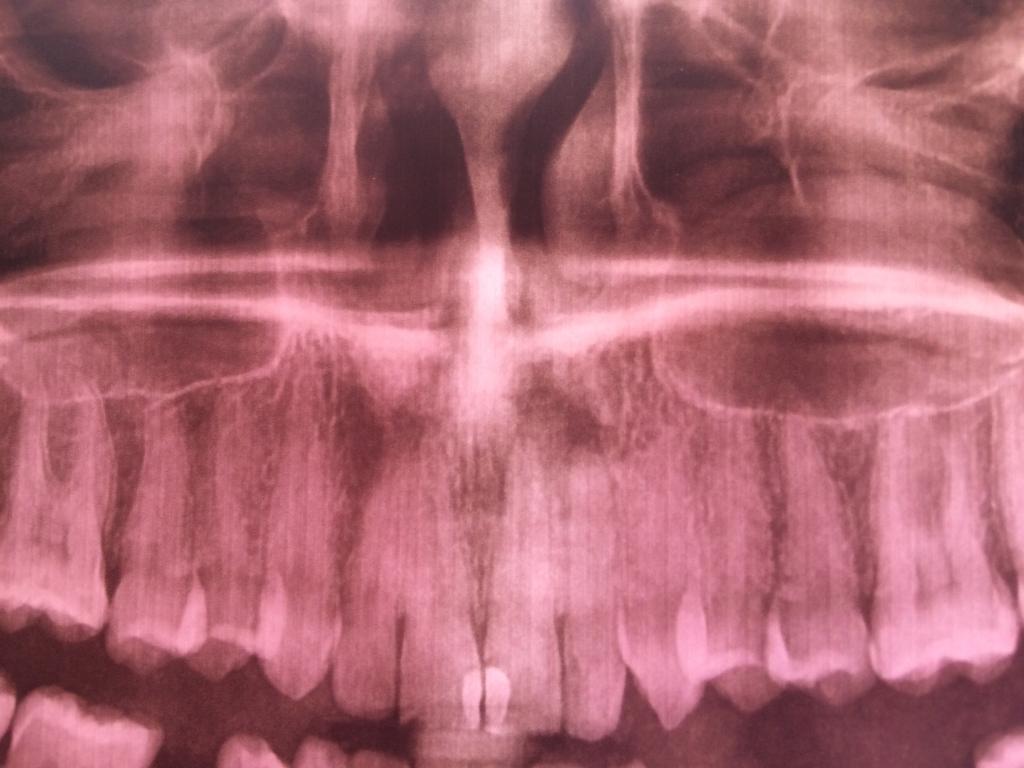

Здравствуйте, подскажите клинику с лазерным удалением кисты, или может ее можно вылечить? Была в клинике Дюна на посёлке Котовского, сделала снимок всей челюсти, они сказали что не знают что это, можно почистить каналы и посмотреть что будет. Сразу же прошла в стоматологическую клинику 5 , сказали что киста, нужно оперировать . Самое главное по какой причине обратилась к врачу это нарыв на десне, гной выдавливаю, пару дней спокойно, после снова набирает. Пожалуйста помогите, не хочу зубы терять.Нажмите на изображение для увеличения

Название: A0B3EA4C-5828-4AEF-A708-771D1F042B1B.jpg

Просмотров: 42

Размер:	73.0 Кб

ID:	12613665Нажмите на изображение для увеличения

Название: 1F2A227A-5E40-4FF0-91A3-15A2061A2B3D.jpg

Просмотров: 40

Размер:	40.3 Кб

ID:	12613666

Здравствуйте, подскажите клинику с лазерным удалением кисты, или может ее можно вылечить? Была в клинике Дюна на посёлке Котовского, сделала снимок всей челюсти, они сказали что не знают что это, можно почистить каналы и посмотреть что будет. Сразу же прошла в стоматологическую клинику 5 , сказали что киста, нужно оперировать . Самое главное по какой причине обратилась к врачу это нарыв на десне, гной выдавливаю, пару дней спокойно, после снова набирает. Пожалуйста помогите, не хочу зубы терять.Вложение 12613665Вложение 12613666

...пролечить зуб, запломбировать канал...возможно, и хирургия не понадобится...